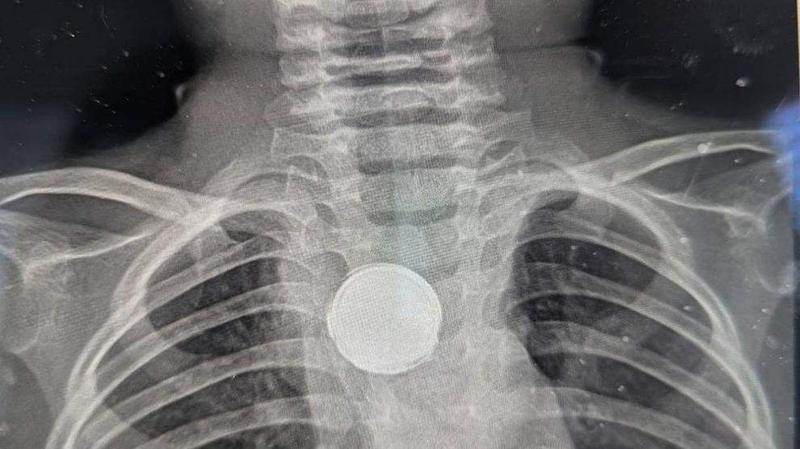

Radiografía del niño estadounidense que se tragó una pila

Erica lo volvió a llevar al médico, pensando que fuera un problema de reflujo. Pero la madre, sabía que pasaba algo más. Decidió llevarlo a otro pediatra que pidió una radiografía de Luke. "Les vi poner una mirada extraña", dijo Erica. Los médicos le preguntaron si su hijo había tragado una moneda o si usaba un collar con un botón, a lo que respondió que no, siendo Luke llevado a urgencias inmediatamente.

"(Los médicos) decían, 'no hay forma de que sea una pila porque comienzan a corroerse en tan solo dos horas'", prosiguió su relato Erica.  Los médicos dijeron a los padres de Luke que tenía algo plateado en el pecho, pero que sería peligroso sacar ese objeto sin una cirugía completa.

Después de la operación los médicos le habían encontrado una batería de litio pegada al interior del esófago de Luke. La pila estaba envuelta en cinta aislante, y se cree que eso fue lo que le salvó la vida al niño y evitó que se intoxicase letalmente, según los médicos. La pila había permanecido alojada en la garganta de Luke durante cinco semanas y había dañado el tejido esofágico, que los cirujanos intentarán reparar ahora.